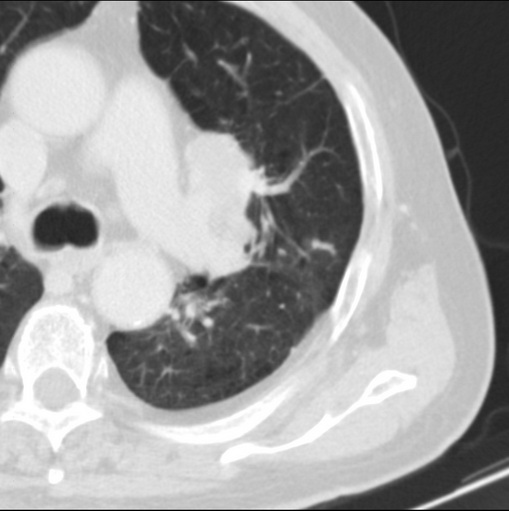

男性患者 81岁 咳嗽 咳痰 咯血

左肺中心型肺癌并:1.左肺阻塞性肺炎;2.纵隔淋巴结肿大;

考虑左上肺癌并阻塞性肺炎,左肺转移、左肺门及纵隔淋巴结转移。

肿块贴近左肺门,包绕左上肺动脉,形态不规则。肿块增强扫描中度强化。纵膈内主动脉弓左旁间隙、气管隆突前、下间隙见多枚淋巴结影。综上考虑左侧中央型肺癌可能性大。图片没有完整上传,尤其是左肺上叶支气管分支层面没有上传,因此不好判断是叶支气管中断还是段支气管中断。另外,下图红色部分所示是“黏液支气管征”吗?